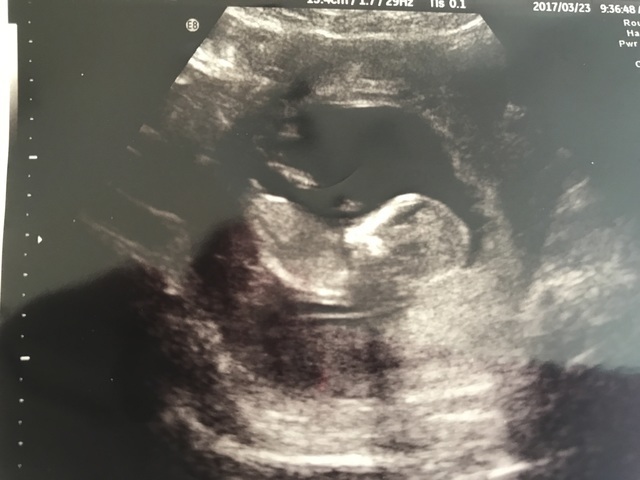

7週0日(7w0d・性別不明)|ゆぅこけん さん(31歳)

エコー写真撮影時のエピソード:左側が頭、右側が胴体だと思うのですが、背中から撮ったやつだと思うのですが、足がパカーン!

これはすぐ性別もわかりそうなかっこですよね、、笑

お行儀の悪い赤ちゃんに産まれそうです、、笑

みんなにこのこはお行儀悪いから男の子やわ!とか言われてます笑